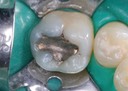

Joe Cha #3 pre-op